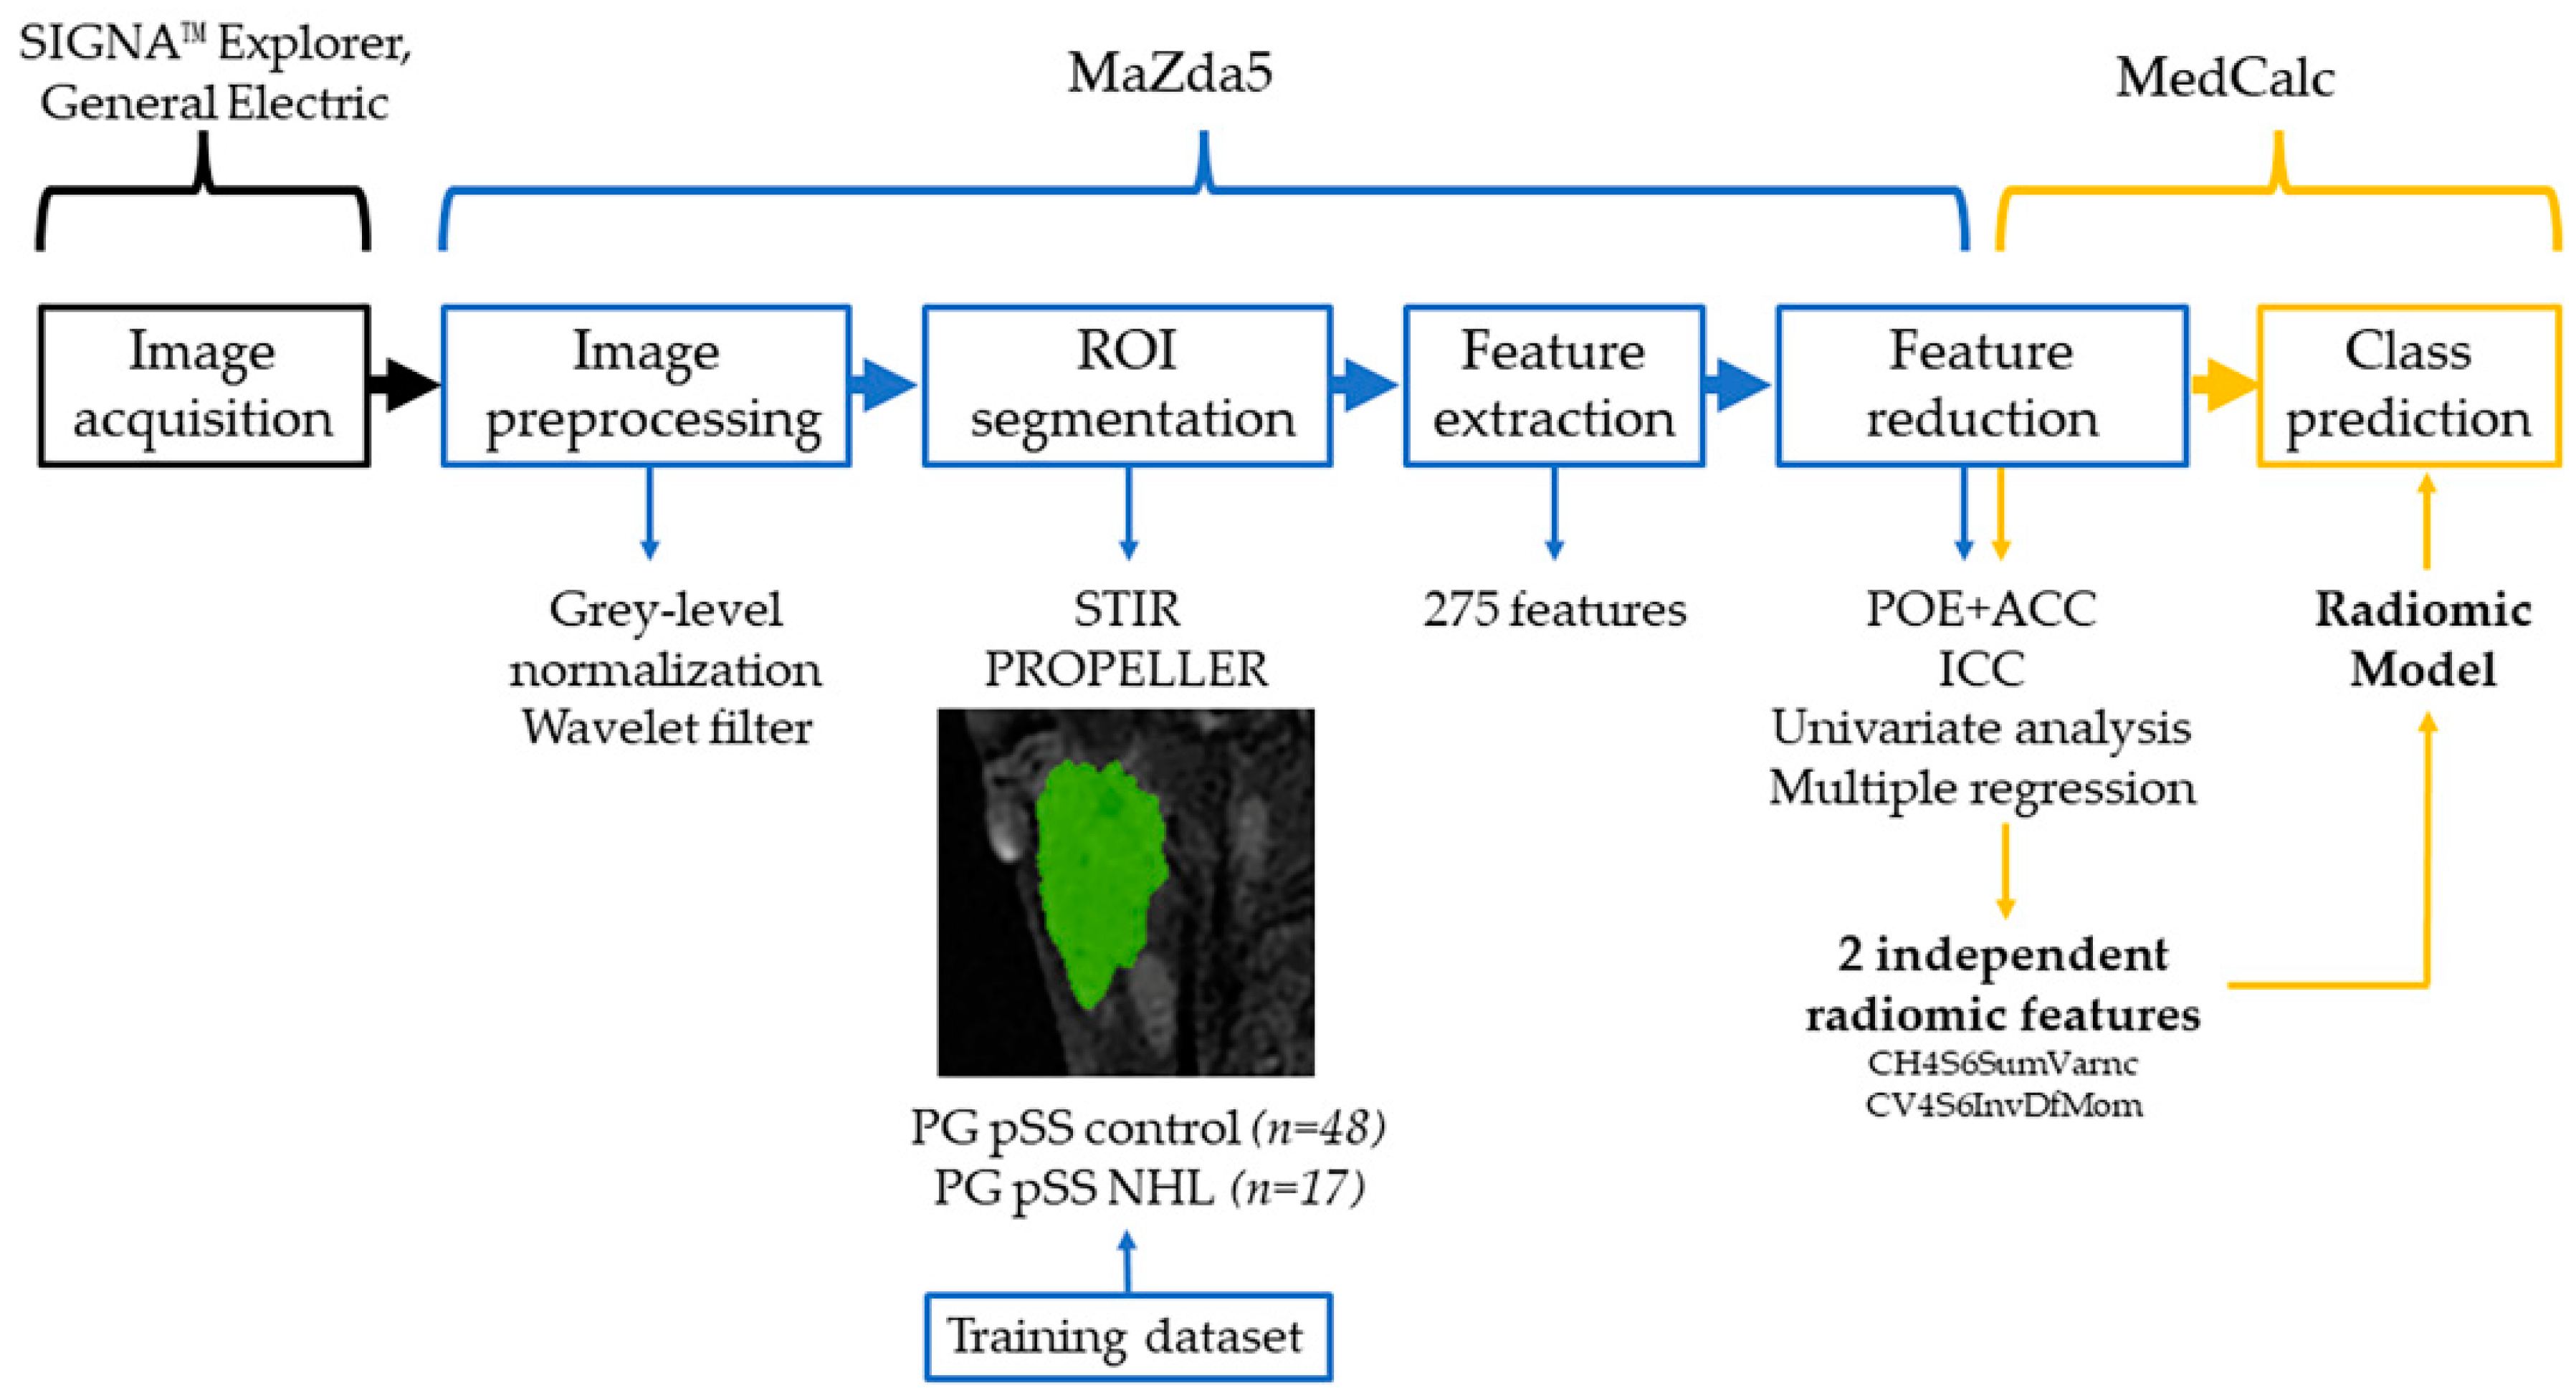

2.3. Texture Analysis Protocol and Statistical Analysis

2.3.1. Image Preprocessing and Segmentation

2.3.2. Feature Extraction

2.3.3. Feature Selection and Statistical Analysis